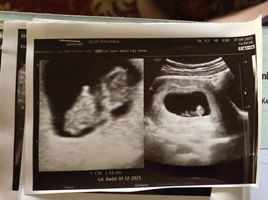

Normal gak bun usia 6w5d tp masih kelihatan kantungnya aja dan ukurannya udh 2.42cm

normal saya kmren jg gt 6w5d masi kantong trs stlah 1bln 0as usg lg janin y dh ada malah lincah bgt mo d print hsl usg y mlh salto" berfikir positif aja bun insyaallh usg berikut y hasil y memuaskan amin...

normal bun krna usia kehamilan masih kecil, coba nnti 10/12week bunda usg lagi insyaallah udah ada janin sma djj . aku juga ngalamin bun, hpht bukan patokan kita gak tau pembuahannya kpn . aku aja selisih 1minggu sama hpht

Saya juga 6w masih kosong bun,lewat transvaginal pun juga sama tapi itu 6w diukur dari kantongnya bun. Disuruh balik 2 minggu lagi bun dan Alhamdulillah udah ada adeknya dan djjnya, usia kehamilannya ternyata baru 6w bun.